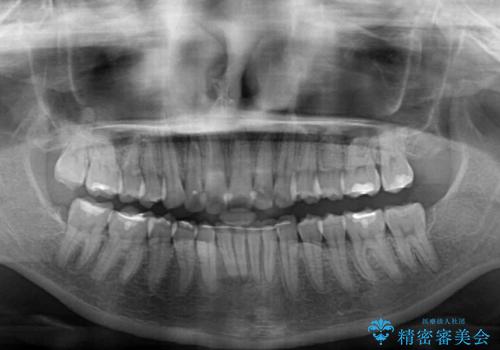

深い咬み合わせと前歯のデコボコ インビザラインによる矯正治療

治療途中では、左右ともに奥歯が咬みにくい状態が続き、問題なく噛めるようになるまでに長期間を要しました。

一方で、デコボコや下顎の前歯が隠れてしまうほどの深い咬み合わせはしっかりと改善されました。